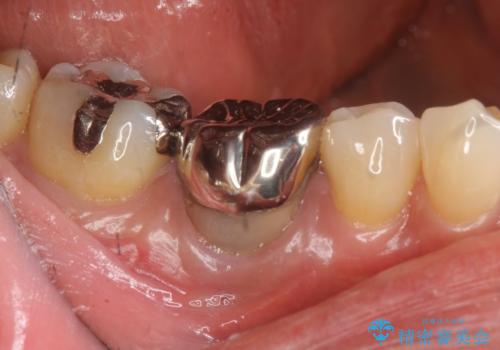

- 長年気になっていた、目立つ銀歯を白くしたい。とセラミック治療を希望され来院されました。

銀歯を除去したのち、精度の良いジルコニアセラミッククラウンでクラウンのやり替えを行っていきます。